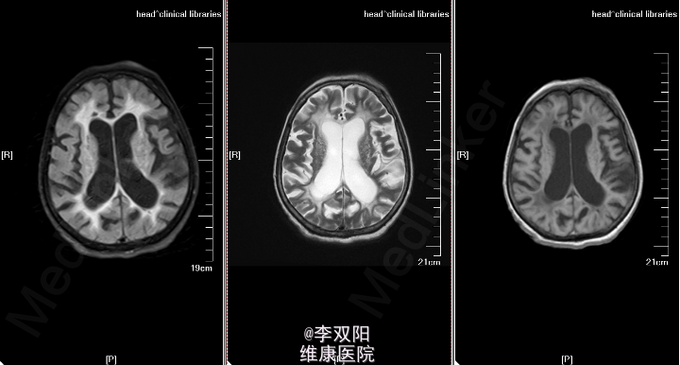

查体:体温36.2℃,脉搏58次/分,呼吸20次/分,血压150/90mmHg。轮椅推入病房,查体合作。皮肤巩膜无黄染,双肺呼吸音清,未闻及罗音,心率58次/分,律齐,无病理性杂音,腹部平软,肝脾肋下未触及。 神经系统专科查体:神志模糊,失语,双瞳孔同大同圆,直径3.0mm,对光反射灵敏,眼球各方向可活动,无眼震及复视,鼻唇沟对称,咽反射(+),伸舌不合作,四肢肌力2级,肌张力增高,肱二头肌、肱三头肌肌腱及膝反射、跟腱反射均对称,感觉及共济运动检查不合作,Hoffmann征L(-),R(-),病理征:Babinski征L(+),R(+),颈无抵抗,Kernig征(-)。 辅助检查:头颅CT扫描示:双侧基底节区及丘脑区斑片状低密度影,双侧脑室周围及双侧半卵圆中心见片状密度减低区,边缘模糊不清。双侧脑室扩张,脑沟裂增宽,中线结构居中。 头MRI+DWI:双侧基底节区及丘脑区斑片状低密度影,双侧脑室周围及双侧半卵圆中心见片状密度减低区,边缘模糊不清。双侧脑室扩张,脑沟裂增宽,中线结构居中。